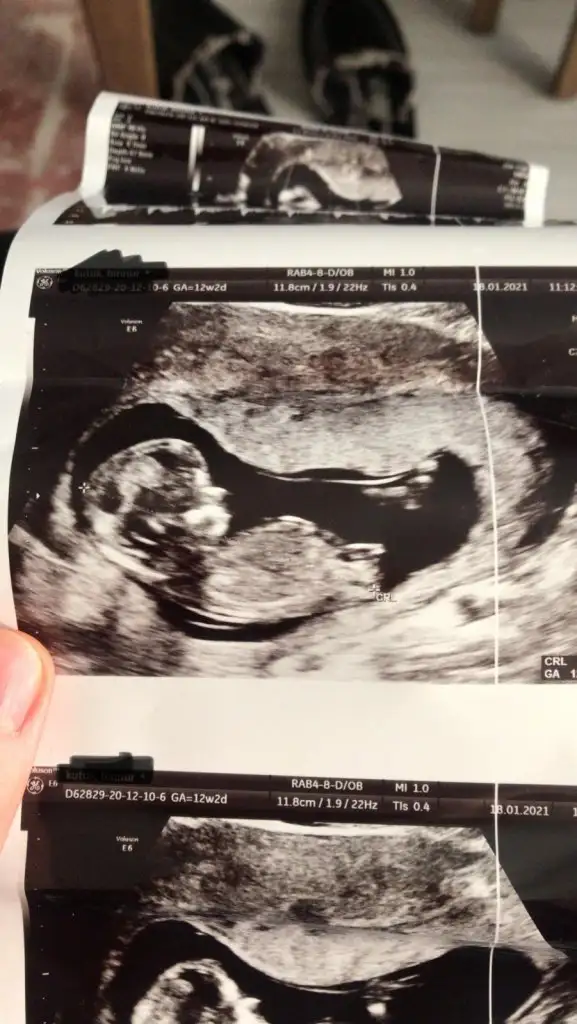

Buradaki hanımların nub teorisine göre kız gibiEki Görüntüle 2764421 Eki Görüntüle 2764422 Eki Görüntüle 2764423 Tahminde bulunur musunuz arkadaşlar